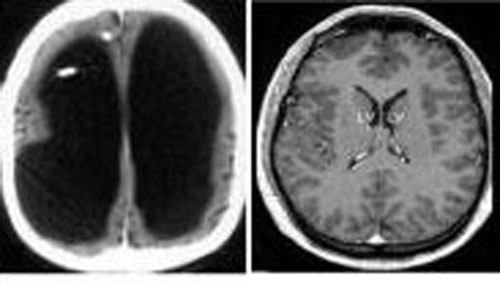

法国“无脑人”震惊医学界 来源:东楚晚报时间:2007-7-22 10:43:00标签: 本报综合消息法国医生日前在为一名44岁法国男子的脑部做CT和核磁共振

令人匪夷所思的是,虽然颅内充满大量液体,大脑组织被挤得只剩一点点,可是这名44岁的“无脑人”正常生活并未受到影响。事实上,他不但娶妻生子,还是一名政府公务员。脑力

在Lorber教授眼里,这样的案例虽然特殊,但并不少见,因为仅他个人就确定了几百例大脑半球都非常小、而智力正常、生活学习跟普通人没有差异的“无脑人”,他形容这些人有着